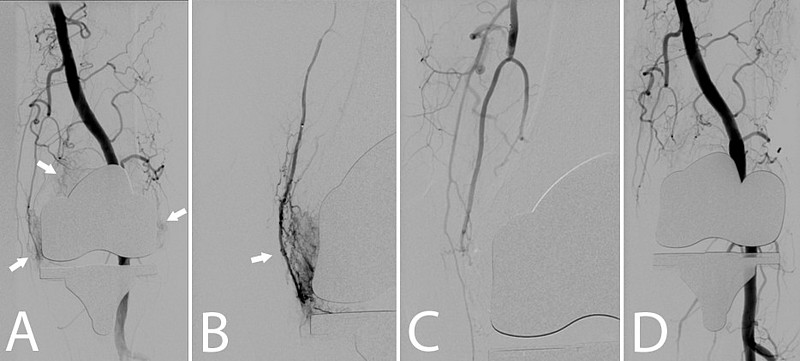

Nach einer lokalen Betäubung (Lokalanästhesie) in der Leiste wird ein kleiner Katheter in die Hauptschlagader des Beins (A. femoralis com.) eingebracht und am Beispiel des Kniegelenks zu den versorgenden Gefäßen vorgeführt. Die einzelnen kleinen Gefäße, welche das Kniegelenk versorgen werden gezielt (superselektiv) mittels eines Mikrokatheters (Durchmesser 0,51 mm) sondiert. Lässt sich eine Entzündungsreaktion durch eine vermehrte Kontrastmittelaufnahme („Blush“) beweisen, wird ein Medikament gespritzt, was die kleinsten Gefäße verschließt (Embolisation). Nach der Embolisation werden die Katheter wieder entfernt und die Punktionsstelle mittels manueller Kompression verschlossen. Eine Bettruhe von mindestens 6h und ein Druckverband für 24h sind nach dem Eingriff notwendig. Deshalb ist für Sie ein Krankenhausaufenthalt mit einer Übernachtung zu planen.